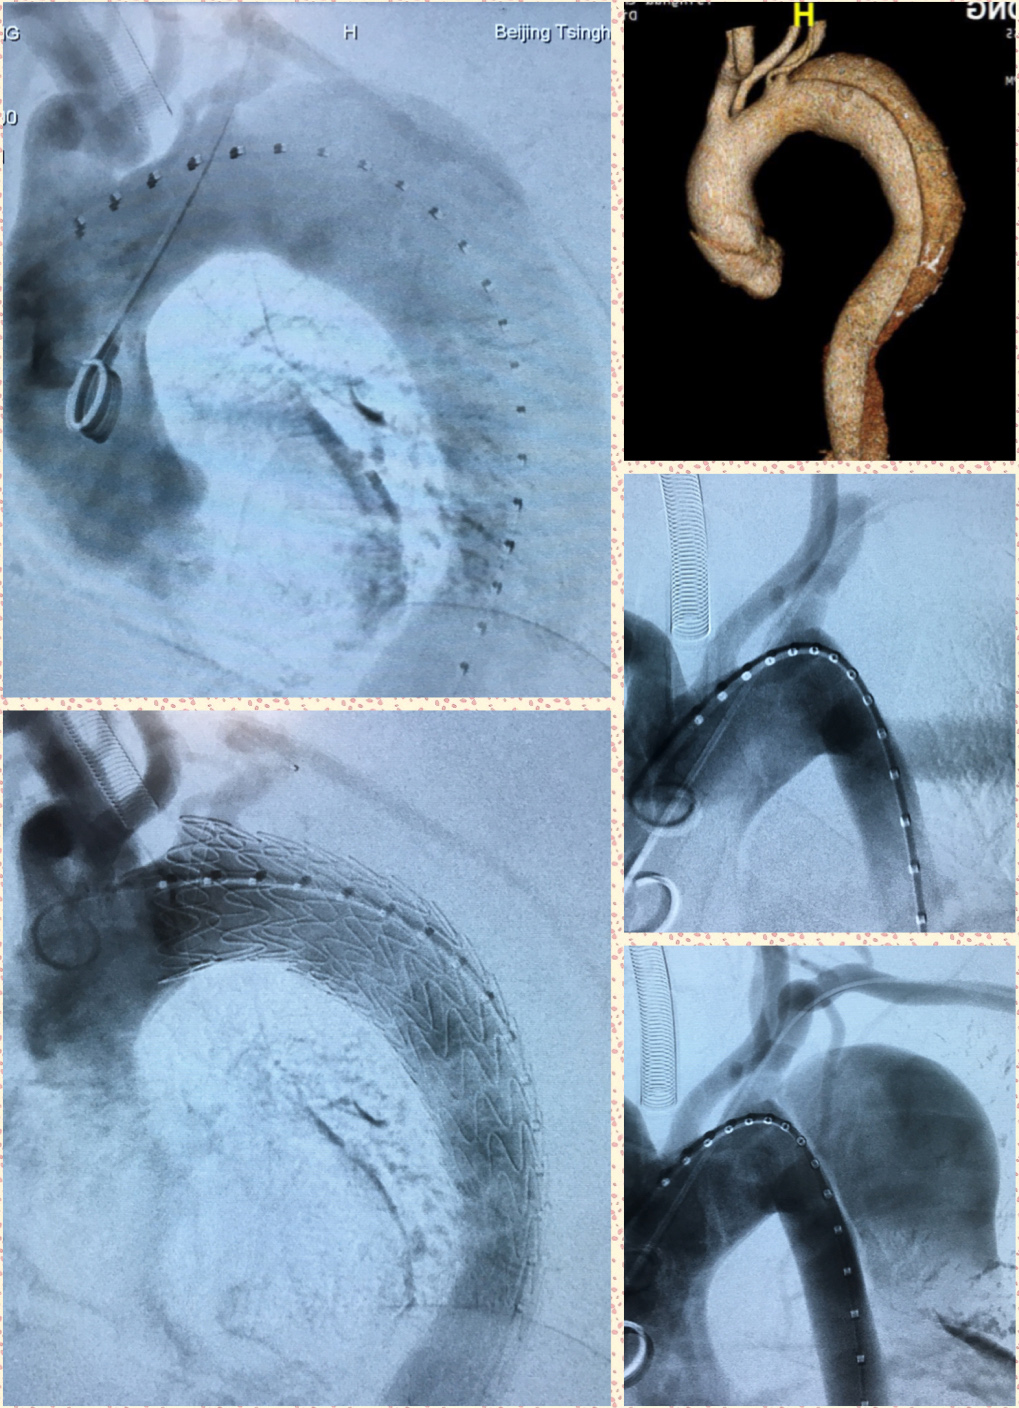

图为主动脉夹层腔内修复术中影像

接受手术的是位50岁男性患者,原本因阻塞性睡眠呼吸暂停低通气综合征(OSAHS,鼾症)就诊于耳鼻咽喉头颈外科。进行全面健康检查时,经胸主动脉及腹主动脉CT血管成像(CTA)检查,提示主动脉夹层内膜破裂,夹层累及范围自左侧锁骨下动脉以远至左侧髂总动脉。耳鼻喉科立即联系转诊患者至血管外科。在麻醉科、手术室的配合下,血管外科吴巍巍主任带领团队,成功为该患者实施微创的胸主动脉夹层腔内修复术,术后效果良好。